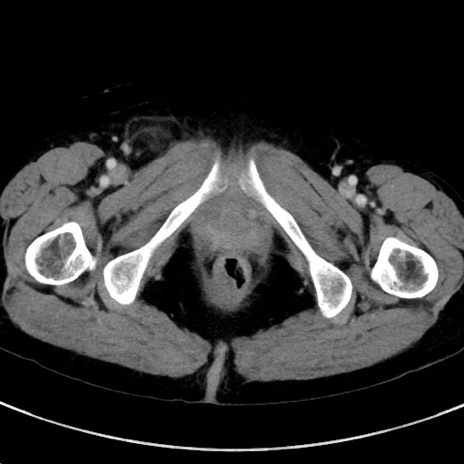

冠状断像

【症例】70歳代女性

【主訴】下腹部痛・嘔吐

【現病歴】2日前より腹痛あり。昨日嘔吐あり。症状改善しないため来院。

【既往歴】胃GISTに対して胃部分切除後。

【身体所見】BT 37.1℃、BP 128/77mmHg、腹部:平坦・軟、下腹部に圧痛あり。

【データ】WBC 10200、CRP 0.31